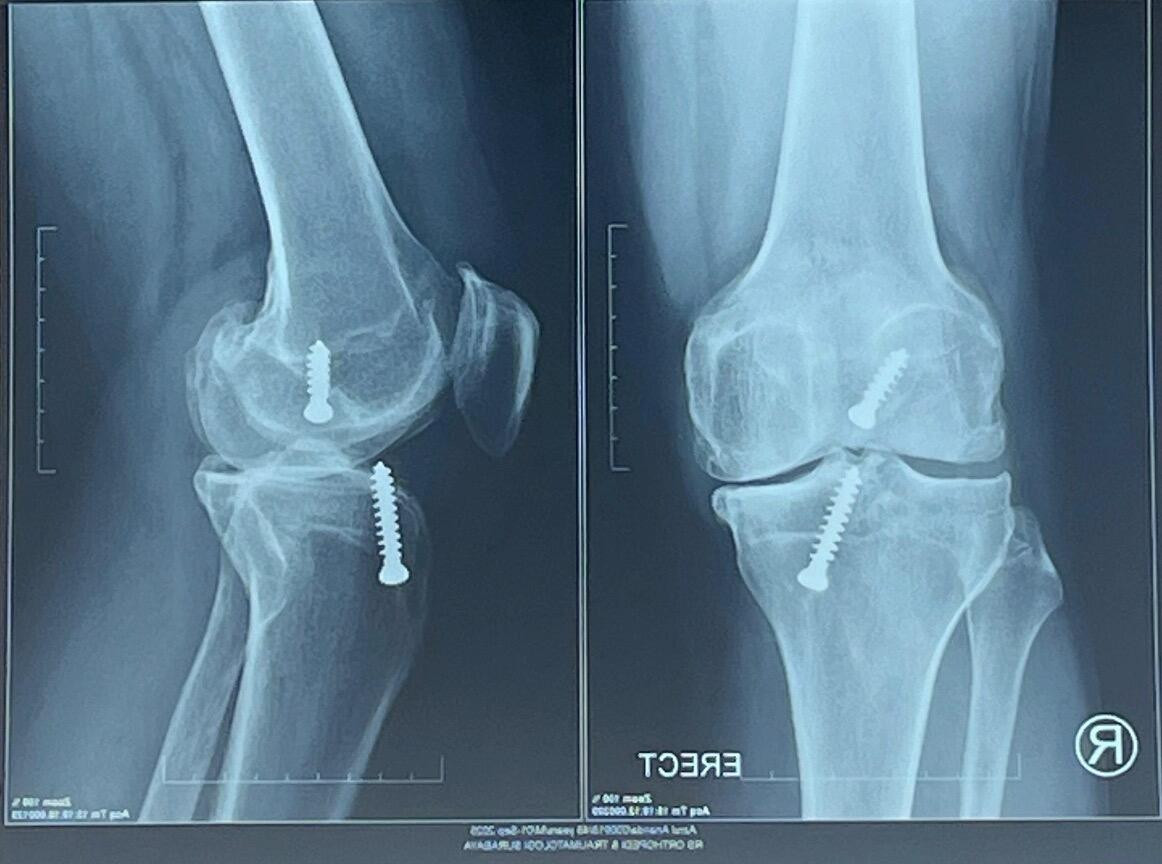

Akhirnya MRI. Hasilnya: Anterior cruciate ligament (ACL) kanan putus total, meniscus sobek, dan ada bone contusion. Langsung operasi, tapi masih metode jadul. Dengan metode open patella, dengan menggunakan dua baut.

Tahun 2025 ini adalah ujung kesabaran saya tentang lutut ini. Hasil x-ray terakhir, sisi dalam lutut kanan sudah OA (osteoarthritis) grade 3-4.

Lutut kanan baru dengan implan dari Amerika.

Menurut Theri, saat lutut saya dibongkar, kondisinya memang parah. Istilahnya "rusak", bahkan "hancur". Meniscus alias bantalan sudah nyaris tidak ada, ACL juga praktis tidak berguna. Tulang-tulang rawan sudah banyak rusak, tulang-tulang muda bertumbuhan tidak aturan mengganggu di mana-mana. Khususnya di belakang lutut, membatasi gerakan menekuk ke belakang.

Jadi memang sudah harus diganti. Kata Theri, implant saya size-nya paling besar. Karena tulang lutut saya besar. "Seharusnya sudah perfect", tegasnya.